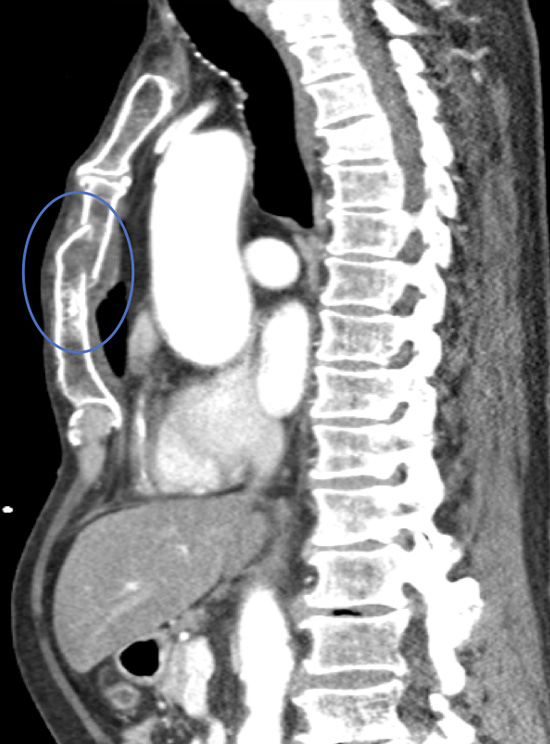

Video of a Chest CT scan taken from the side (sagittal) demonstrating a displaced fracture through the body of the sternum.

Chest CT showing an un-displaced sternal fracture albeit in two places (blue ring)

Sternal x-ray from the side showing significant sternal fracture.